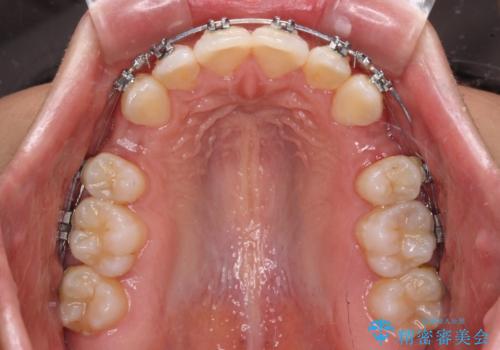

- メタルブラケット

- 出っ歯で唇が閉じにくいとのことで来院された患者様です。

顎先に力を入れないと唇が閉じきれない口元であったので、上下左右の第一小臼歯4本を抜歯して、ワイヤー装置にて矯正治療を行うこととしました。

費用を抑えるため、金属の装置を選択されました。